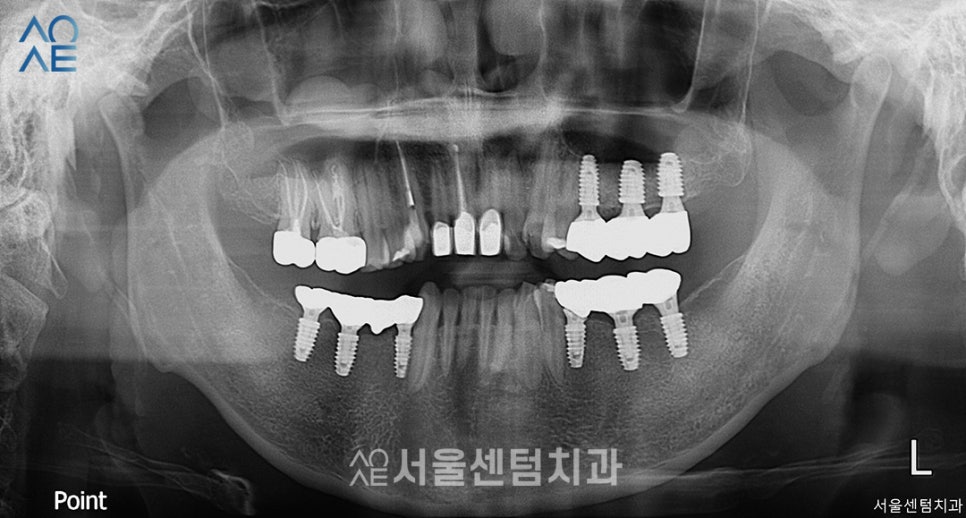

먼저 식립한 오른쪽 부분의 잇몸은 잘 아물어서

바로 보철물 제작도 들어가기로 했습니다.

오른쪽 아래 보철물을 부착한 모습입니다.

치아 기능이 올바르게 회복하기 위해서

브릿지 형태의 보철물로 수복했습니다.

또한 왼쪽 위 임플란트는 2차 수술을 진행했습니다.

일체형과 아닌 것의 차이가 보이시죠?

이렇게 어느정도 임플란트치료가 마무리 되어가고 있습니다.